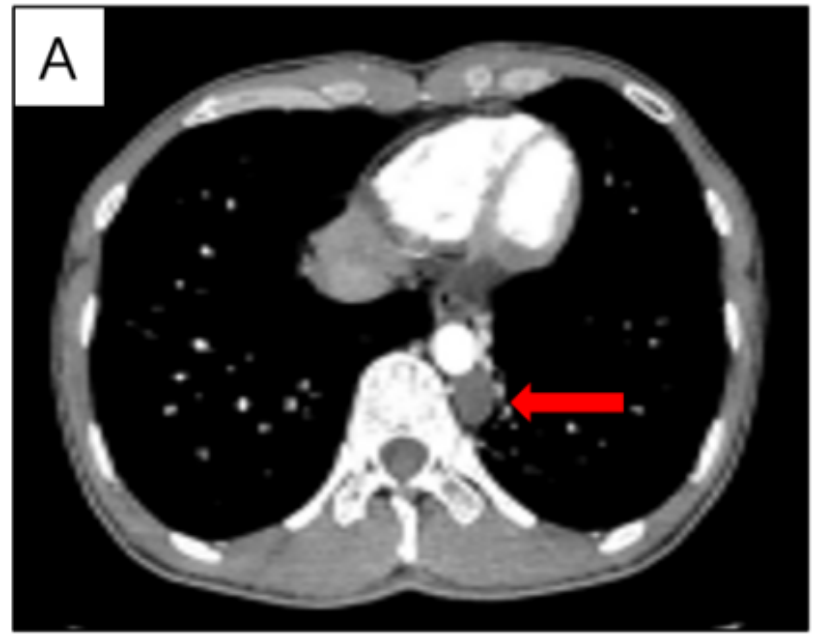

据了解,该患者因体检发现左后纵隔脊柱旁有一个约2.2cm的肿物,考虑为神经源性肿瘤入院。面对这一情况,胸外科、麻醉科及手术室团队进行了充分的术前评估与准备。

手术中,杜小军团队仅在患者胸部开了一个不足3厘米的单孔,凭借精湛的技术,在短短10分钟内便将位于主动脉旁的肿瘤完整切除。依托“无管化”技术的优势,手术采用了对气道损伤更小的麻醉方式,患者在术后苏醒质量良好,不仅无需插管,更能自主活动。在医护团队的陪同下,患者步行走出手术室,全程从手术开始到离开仅用时约半小时。次日复查胸片,显示胸腔内无积气、积液,顺利康复出院。